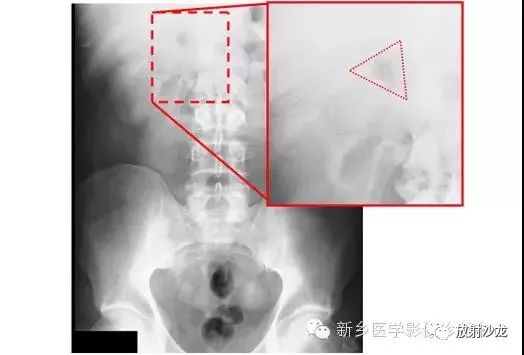

腹痛患者所做的腹部平片。有助于临床诊断的微妙征象是什么呢?

气腹患者摩里逊陷凹存在气体。平片中,靠近11肋的右上象限可见三角形(如在这种情况下)、半圆形,或月牙形的气体集聚。在仰卧位X光片中,右上象限的气体不能解释为肠道内气体,通常为腹腔内游离气体的最早迹象。